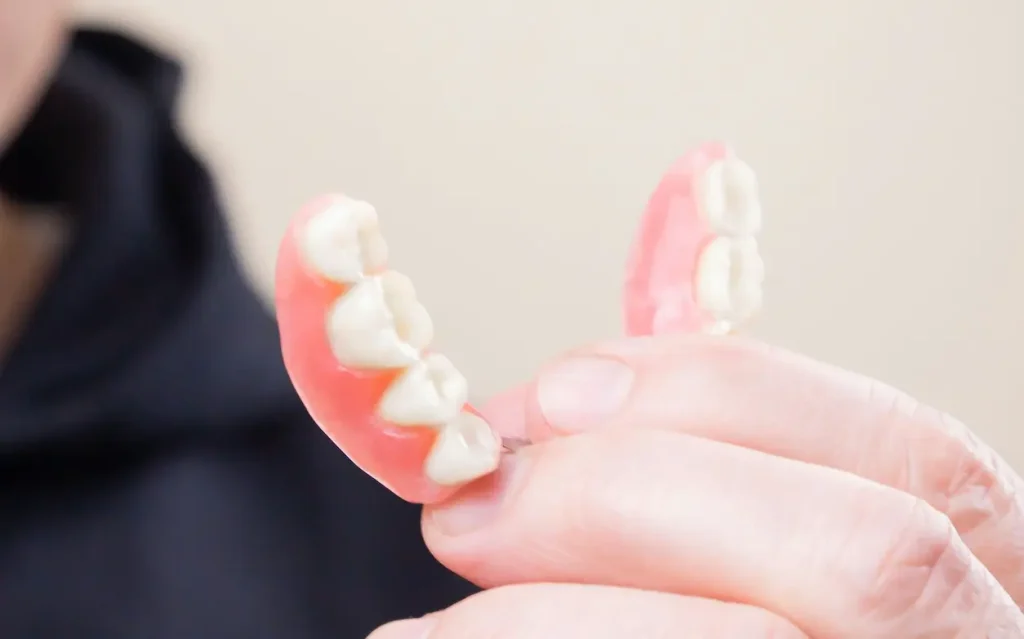

入れ歯

取り外し式の装置で歯を補う方法です。